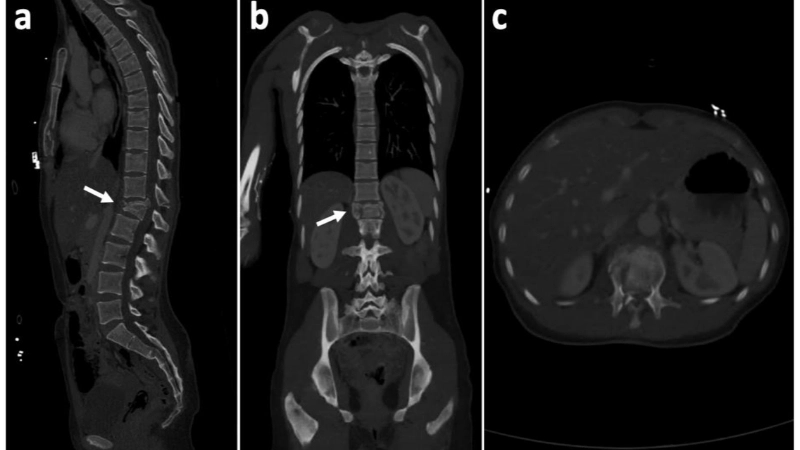

Hình ảnh mô phỏng ấu trùng sán chó lên não